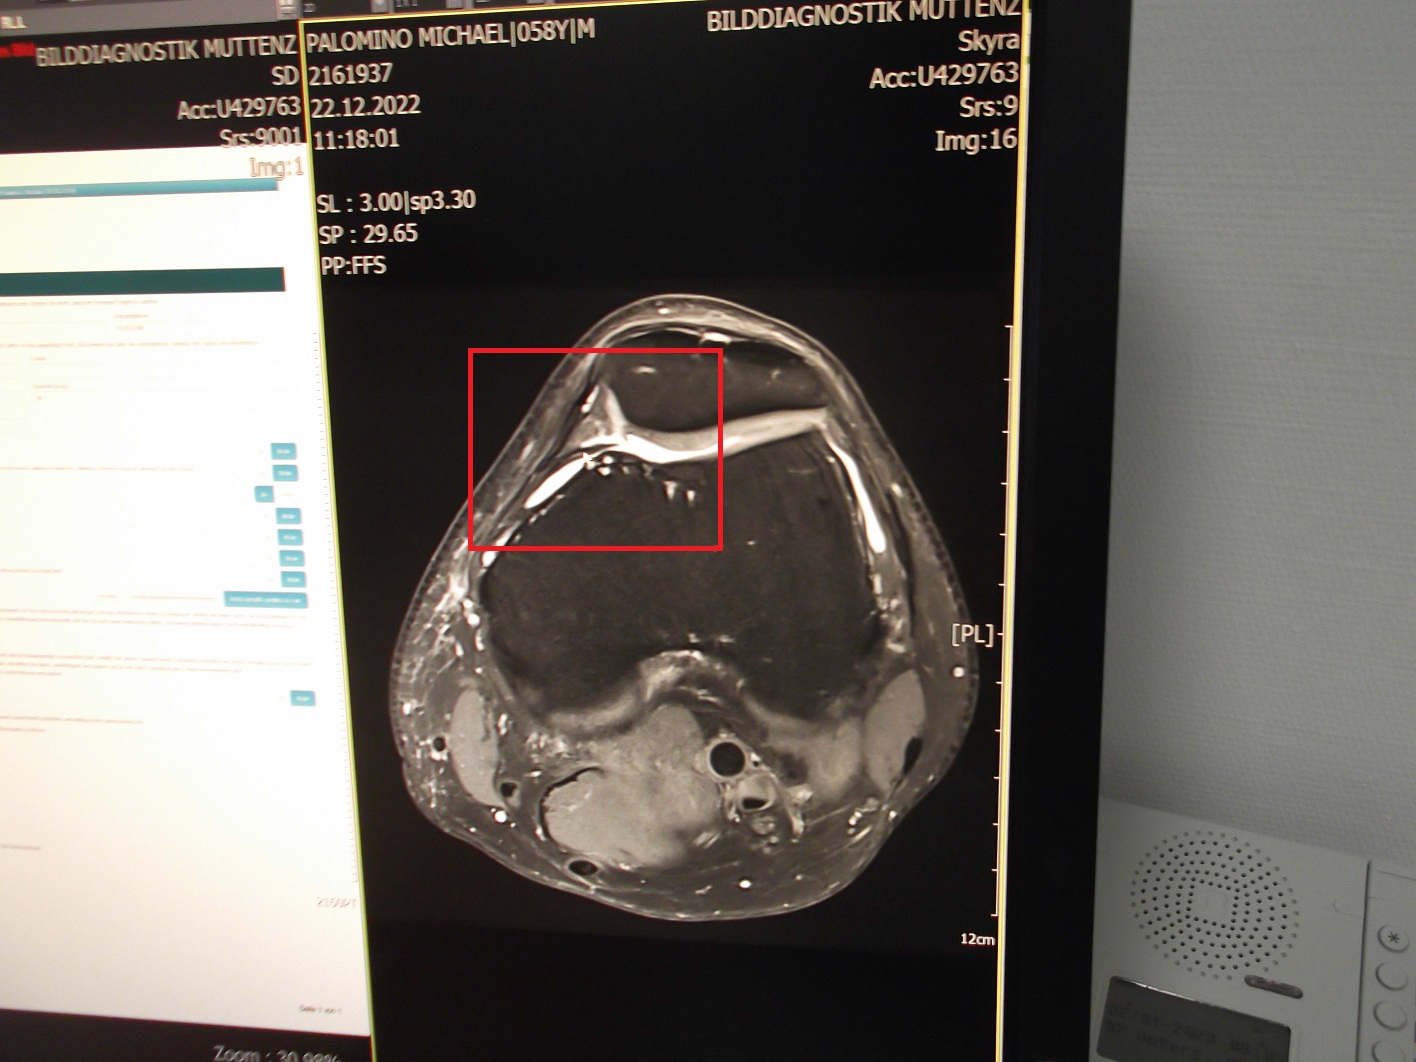

Plica mediopatellaris

-- da ist eine Falte der Gelenkschleimhaut (Synovialfalte) nicht in Ordnung [web01] nach Überbeanspruchung oder Verletzung des Knies [web02]

In der Regel folgt dann eine Untersuchung des Kniegelenks, das zunächst abgetastet wird. Bildgebende Verfahren wie eine Magnetresonanztomographie (MRT), Ultraschalluntersuchung (Sonographie) oder eine Röntgenaufnahme können bei der Diagnose helfen.

[1] Foto mit Plicasyndrom von Michael Palomino 2022